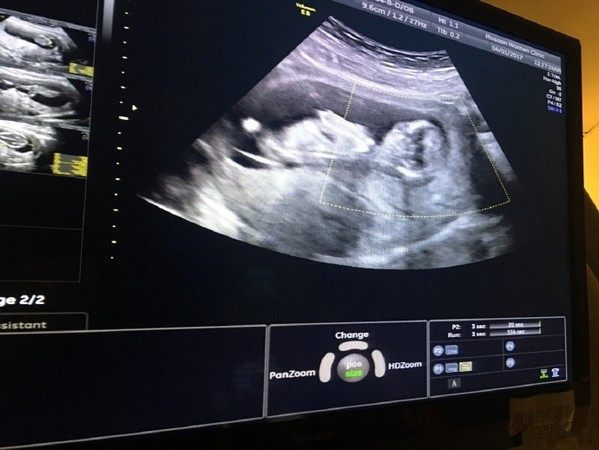

为何预产期过了胎儿还是迟迟不“发动”,究竟预产期过了还没生是什么原因?十月怀胎,一朝分娩,眼看着预产期越来越近,可肚子里的宝宝却迟迟“不发动",宝妈这心里呀,那是一万个着急。可是,这孩子在肚子里呆着,自己不愿意出来,咱着急又有什么办法呢?

一般来说,宝宝出生时间,早于预产期两个星期,或迟于预产期两个星期,都属正常现象。但如果是超出了这个时间范围,那就值得宝妈提高警惕了。因为,超过预产期两周都还没有分娩征兆的话,胎儿在宝妈肚子里的危险性就会随之增加。这是因为胎盘的使用时间是有限的,当胎盘的功能停止时,胎儿就面临缺氧的危险,所以如果已经过了预产期但肚子还没有动静的话,孕妈要到医院做检查,看胎盘功能是否正常,胎儿是否健康,然后听从医生的建议,看是进行剖腹,还是可以继续等待。总而言之,预产期推迟不可怕,宝妈只要放平心态就好了。

预产期本来就只是一个大概时间,并不是非分百准确。据研究调查数据显示,仅有5%的产妇,在预产期当天分娩。也就是说,95%的产妇,均有可能在预产期前生产,或在预产期后生产。这么大的一个比例,说明不管是预产期提前,还是预产期推迟,都属于正常现象(当然,前提是提前不超一个月,推迟不超半个月)。